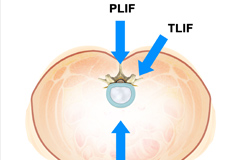

Lumbar Interbody Fusion

Lumbar interbody fusion (LIF) surgery is a surgical technique that involves the removal of a damaged intervertebral disc and the insertion of a bone graft into the disc space created between the two adjoining vertebrae. Bone grafts promote healing and facilitate fusion. Screws and rods are used to stabilize the spine during the healing process.

Minimally Invasive TLIF

Transforaminal lumbar interbody fusion (TLIF) is a minimally invasive fusion of the vertebrae of the lumbar region (lower back). It is designed to provide stability to the spine and treat back and leg pain.